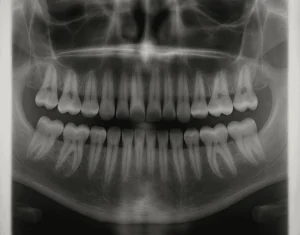

Dentsply Sirona and AADOCR Honor Winning Student Researchers

2025 SCADA Awards winners recognized during the opening ceremonies of the 54th annual meeting of the AADOCR, which was held in conjunction with the annual Canadian Association for Dental Research meeting. Dental manufacturer Dentsply